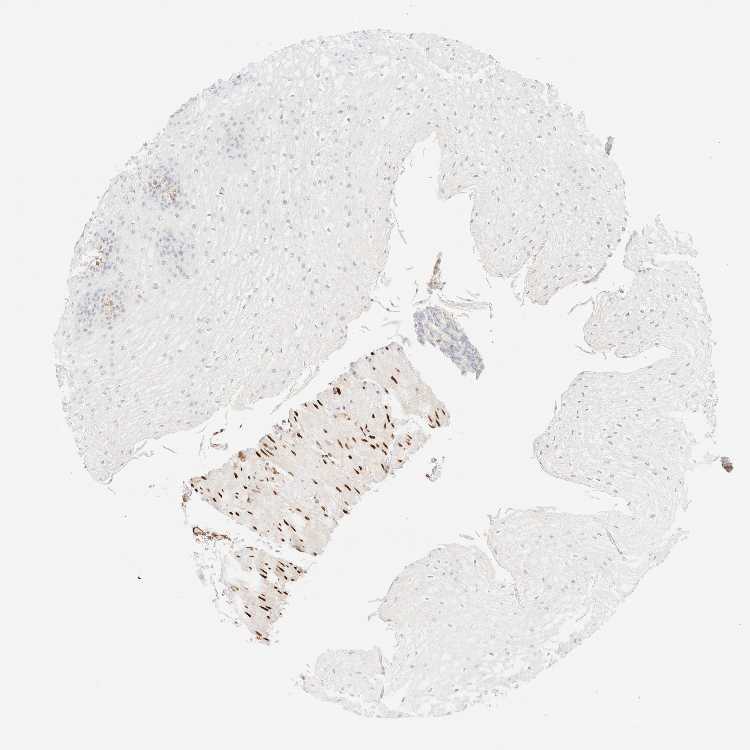

ESOPHAGUS - Antibody stainingi

Antibody staining in the annotated cell types in the current human tissue is reported as not detected, low, medium, or high, based on conventional immunohistochemistry profiling in selected tissues. This score is based on the combination of the staining intensity and fraction of stained cells.

Each image is clickable and will lead to virtual microscopy that enables deeper exploration of all samples and also displays staining intensity scores, fraction scores and subcellular localization as well as patient and tissue information for each sample.

Antibody HPA024318

Squamous epithelial cells Not detected